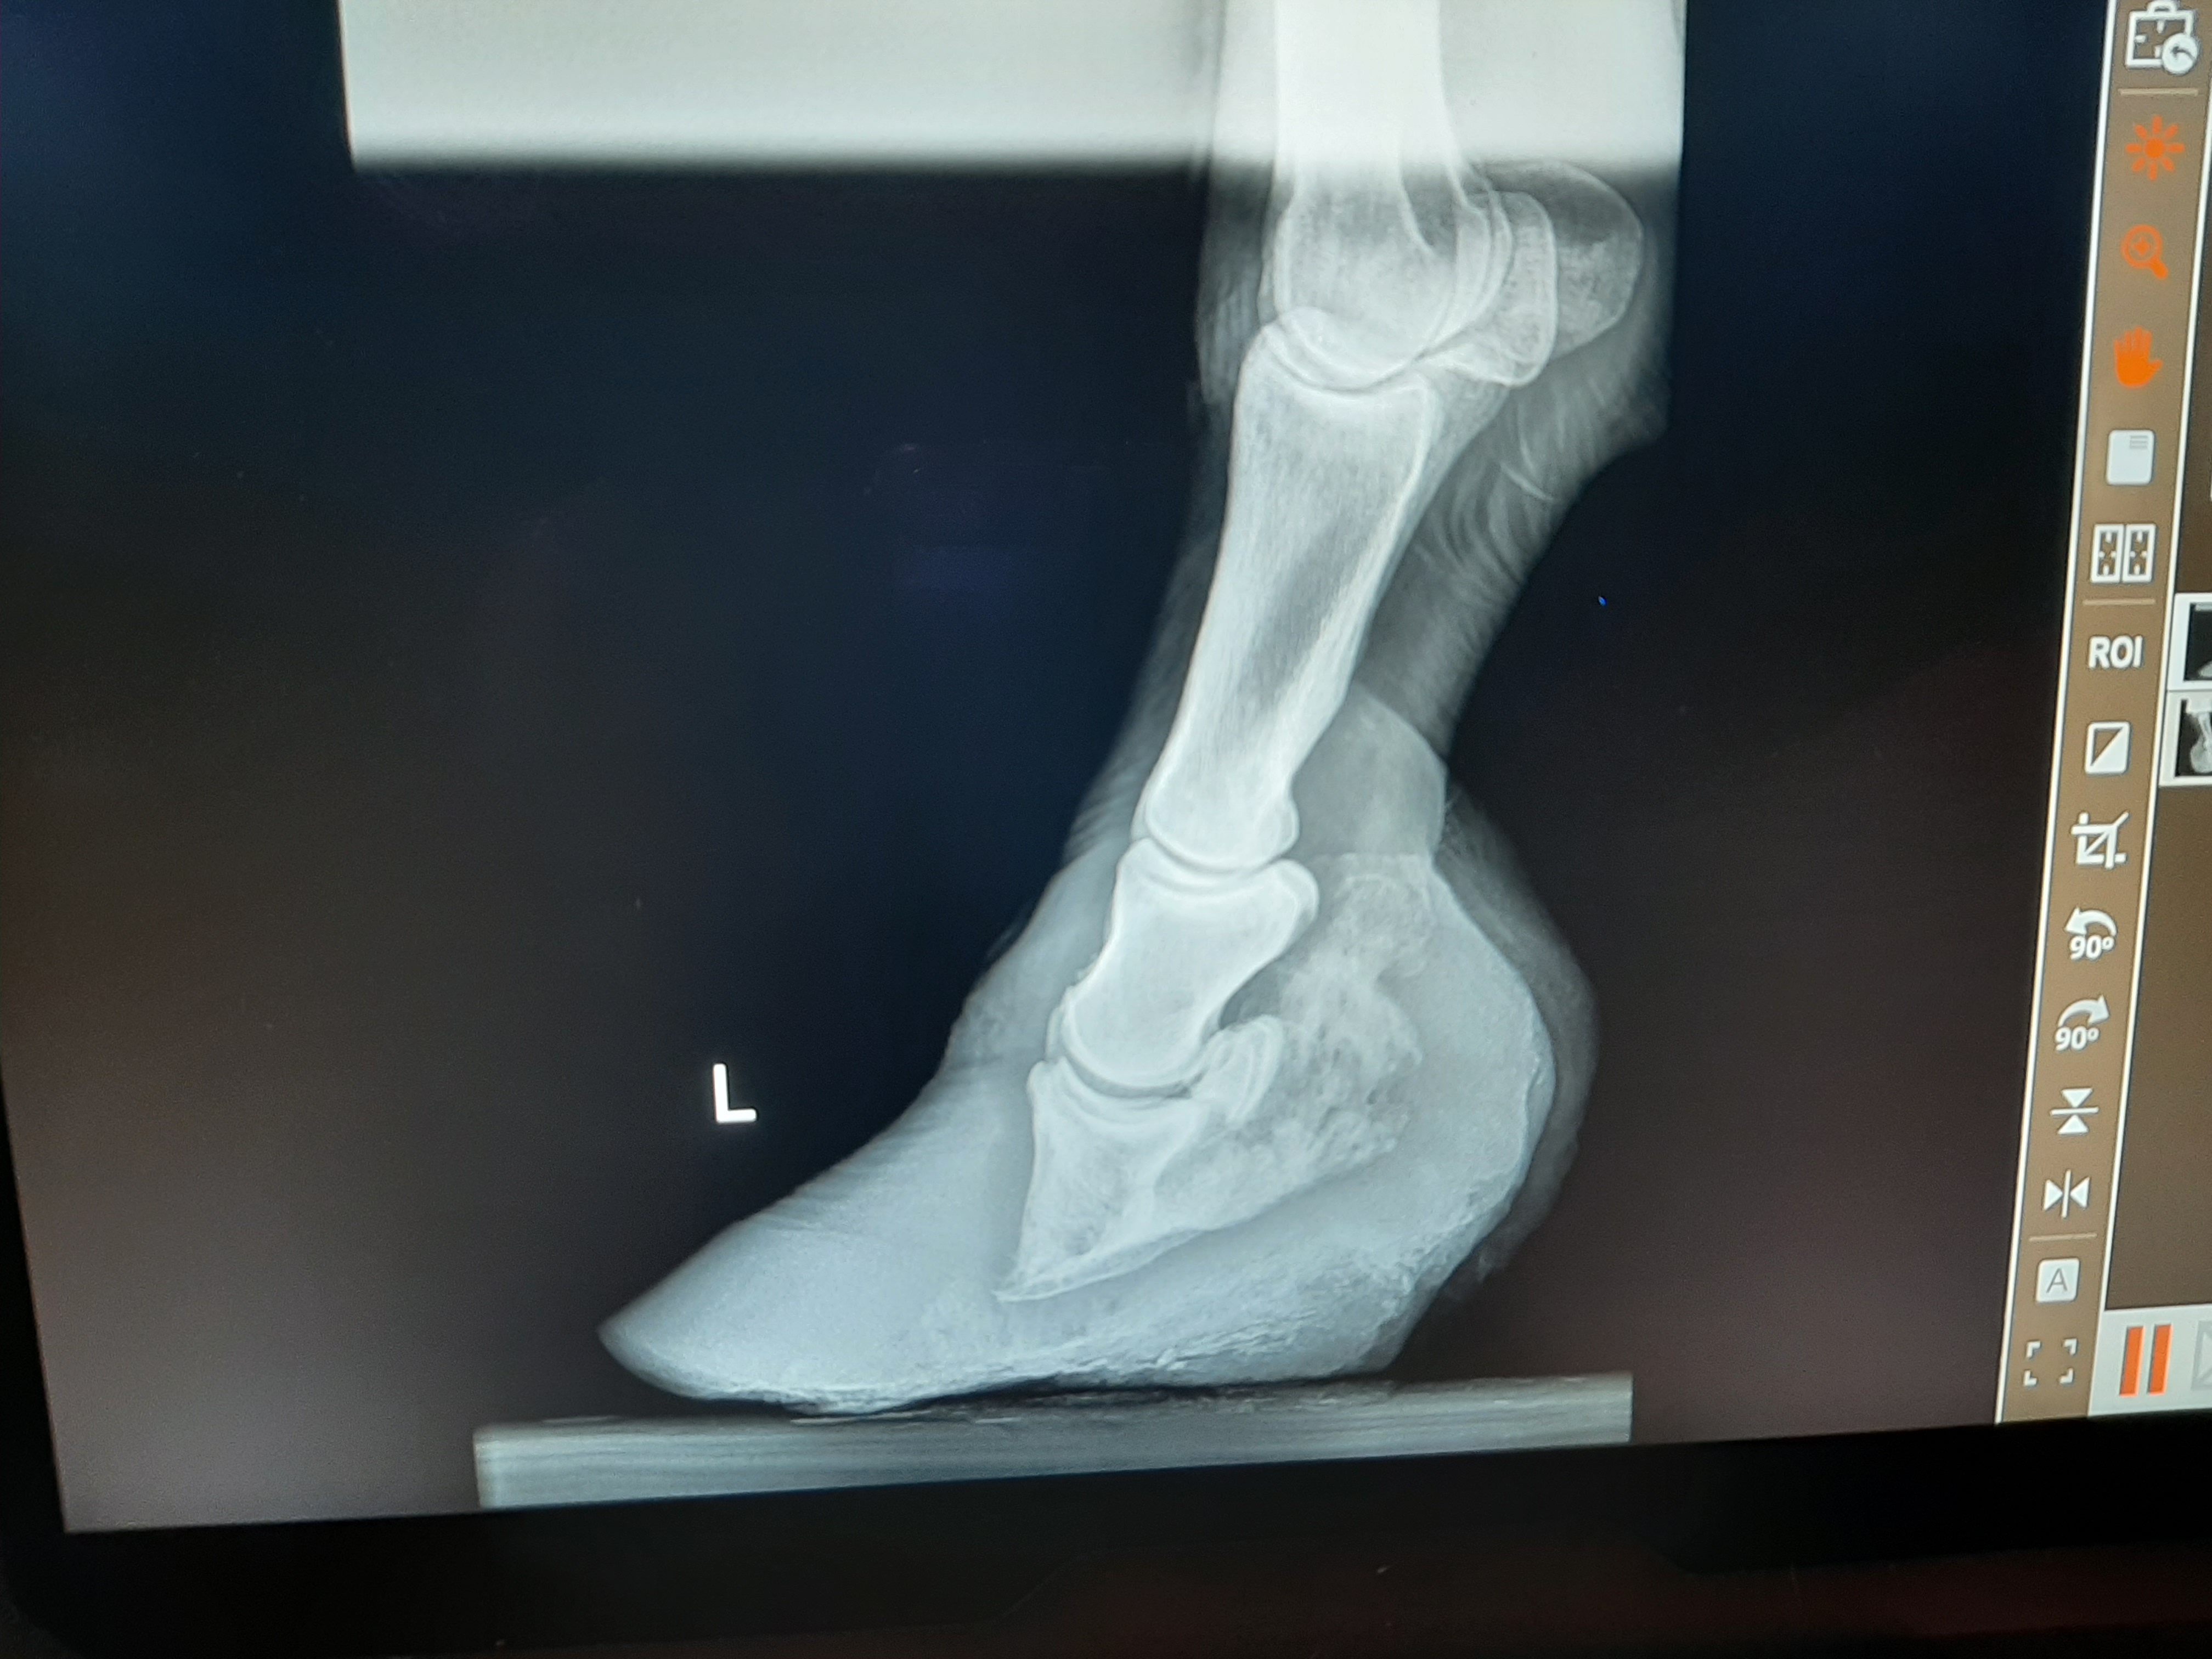

Founder/ Laminitis Case

Before adjustment of hoof. ——– After adjustment of hoof.

This is an example of a founder/ laminitis case that I have been working on. The photos on the left show the beginning of the hoof when I saw it. The photos on the right are after the trim with other x-rays to show the amount of more hoof wall and sole I would have left to take off. Besides the hoof capsule showing that the foot was in bad shape the x-rays show that the coffin bone / P3 is pointed in a downward direction to much. It needs to be pulled back up to go along in the same direction as the outer edge of the hoof wall. Unfortunately horses in this kind of shape are hard to recover to a sound enough shape to be ridden.